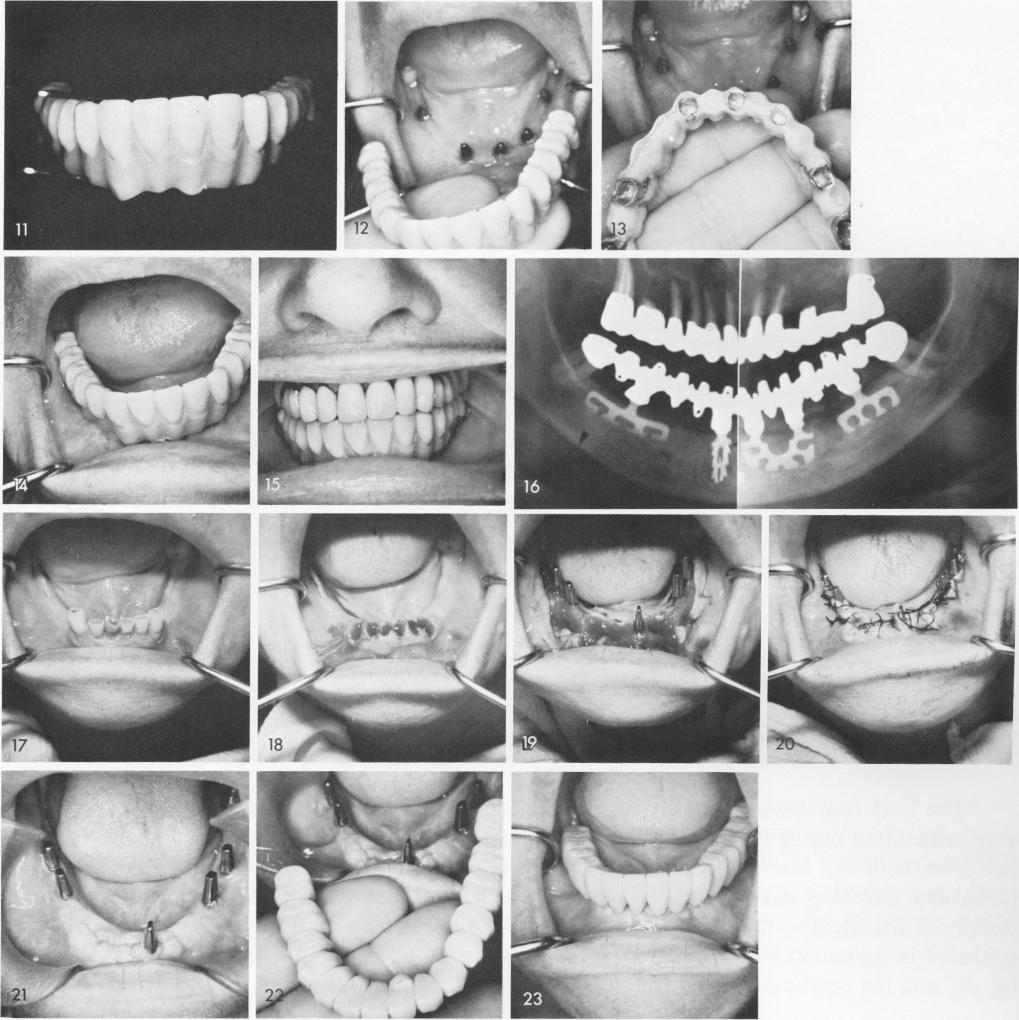

Extremely loose teeth must be extracted, figs. 17, 18. Whenever the sockets are too deep to insert blades a labio-lingual blade can be inserted in a labio-lingual direction directly into the intra-septal bone in between the sockets, fig. 19. After the tissues are sutured, fig. 20, and healing takes place, fig. 21, the completed prosthesis is fabricated and cemented into position, figs. 22, 23. A final x-ray shows the finished case, fig. 24.

1 Insertion of intraseptal labio-lingual blade implant in deep sockets